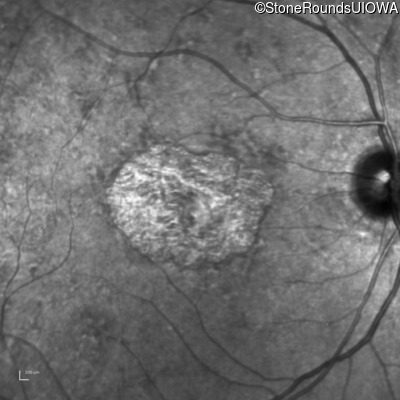

Infrared Fundus Photograph - Right - 20/80 -1

Exemplar